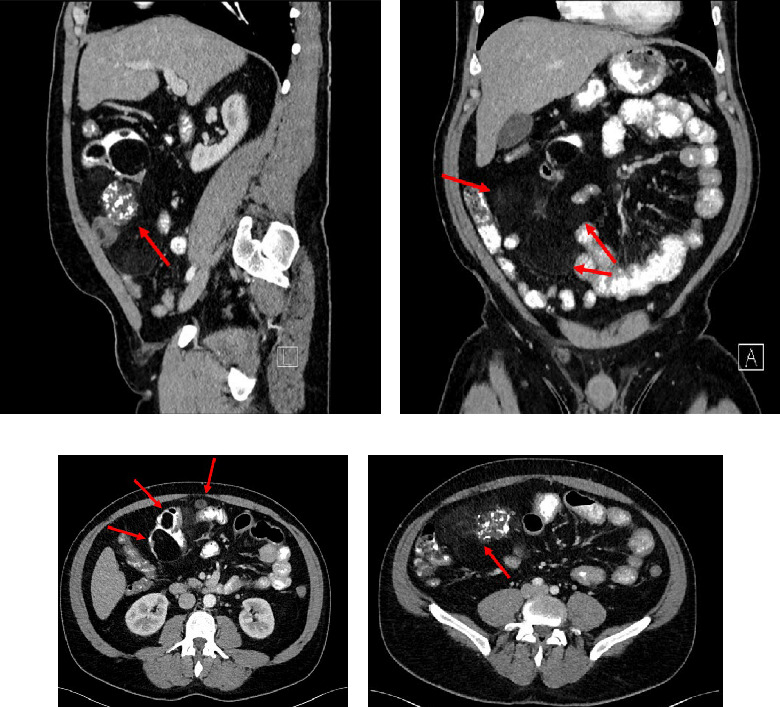

Well-differentiated liposarcomas are common retroperitoneal lesions, but exceedingly rare when primary to the small bowel mesentery, with only a handful of cases reported in the literature. Presented is a patient with a primary mesenteric well-differentiated inflammatory liposarcoma with mucosal extension at high risk for misdiagnosis. A broad differential diagnosis with careful histopathologic observation, ancillary immunohistochemical studies, and fluorescent in situ hybridization for MDM2 amplification are key to make a correct diagnosis. This is especially true if such a lesion was first noted in the lamina propria on histopathology from an endoscopic mucosal biopsy.

Abstract Image